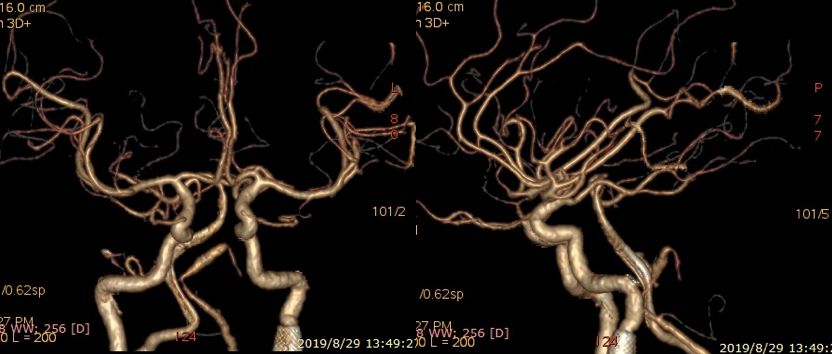

术前右椎动脉造影显示:基底动脉中下段夹层动脉瘤。

术前右椎动脉3D造影

术前左椎动脉造影显示:基底动脉中下段夹层动脉瘤,左侧小脑后下动脉夹层动脉瘤。

根据椎动脉3D造影测量结果,拟选择3.75 mm*35 mm的PED支架。

PED支架顺利释放,与原支架顺利桥接重叠。术后即刻造影显示PED位置满意,动脉瘤内可见造影剂滞留。

DynaCT显示两枚支架形态良好。